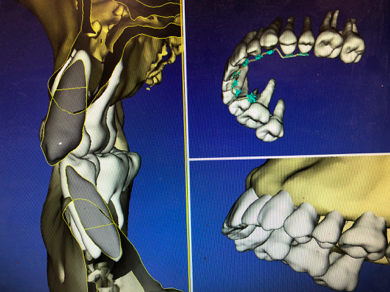

デジタル矯正とは、口腔内スキャナーで採得した歯の精密な3Dデジタル画像とコーンビームCTによる歯根、歯の周りの骨のデータを連動させることで、コンピューター上にお口の中を再現し、矯正治療のシミュレーションを行い、装置にも反映させます。矯正治療は歯ぐきの内側の骨の範囲で歯根を動かす治療です。肉眼では見えない骨の中の歯根の位置も考えられた治療を行うことで、予知性が高く安全な矯正治療が可能となります。二子玉川矯正歯科では、それに加え、口腔内データに沿って作製した矯正用カスタムワイヤーを使用することで、どんな熟練の矯正医よりも精度の高いワイヤー調整が可能となり、治療が遠回りせず期間短縮につながります。